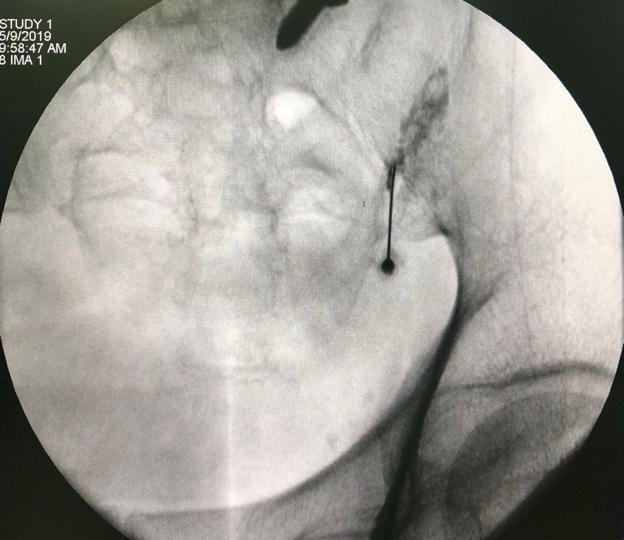

脊柱关节炎无法通过放射资料进行定位,那么怎么确定是脊柱小关节炎性痛呢?这时就要用到我们脊柱外科独门绝招--小关节注射。小关节注射,就是通常说的“封闭”,这是一举两得的既可以帮助诊断又有治疗作用的特殊技术。医生把麻药精准地打到小关节里面,如果疼痛减轻说明这个小关节就是炎症元凶;同时还可以进一步治疗,过1周再注射麻药和激素或者透明质酸钠到小关节,能够较长期的减轻疼痛。

脊柱小关节注射一般比膝关节要复杂一些,X透视下才能找到小关节的缝隙,所以一般要在手术室操作,相当于精确制导的封闭,而不是“盲打”。精准的小关节注射可以达到60-70%有效率,可以维持2-3个月,有些人急性期过后甚至可以数年不发作。